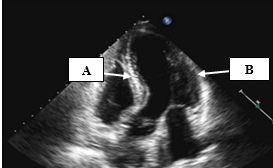

These two vessels (name the vessels and corresponding letter) feed.tje coronary arteries, supplying the heart with oxygenated blood.

What are the coronary sinus's, letters A and B?

This vessel supplies the anterior wall and the apex with blood. (Vessel name and corresponding letter)

What is the left anterior descending (LAD), letter A?

The walls represented by A and B

What is A - Antero septum and B- anterolateral?